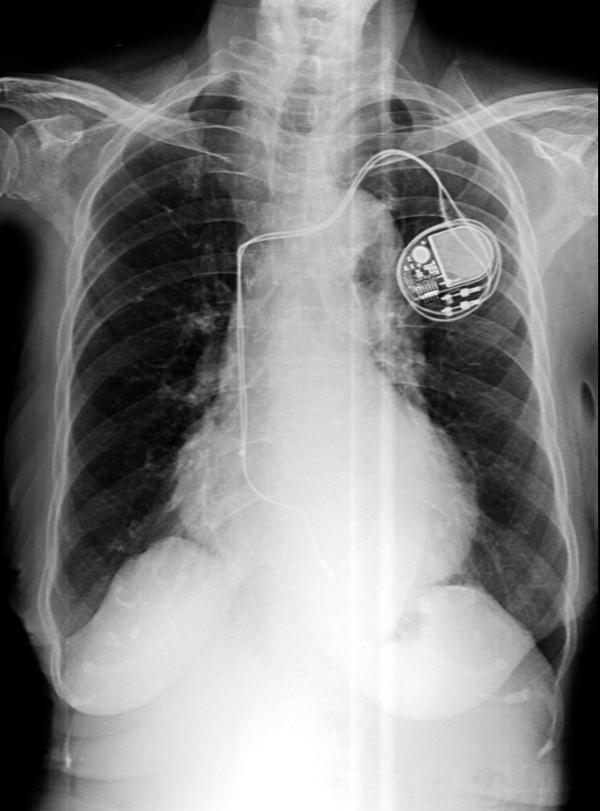

Pacemaker Surgeries Doctors in Pune for Reliable Heart Rhythm Management

Pacemaker Treatment in Pune for Steady Heart Rhythm Support